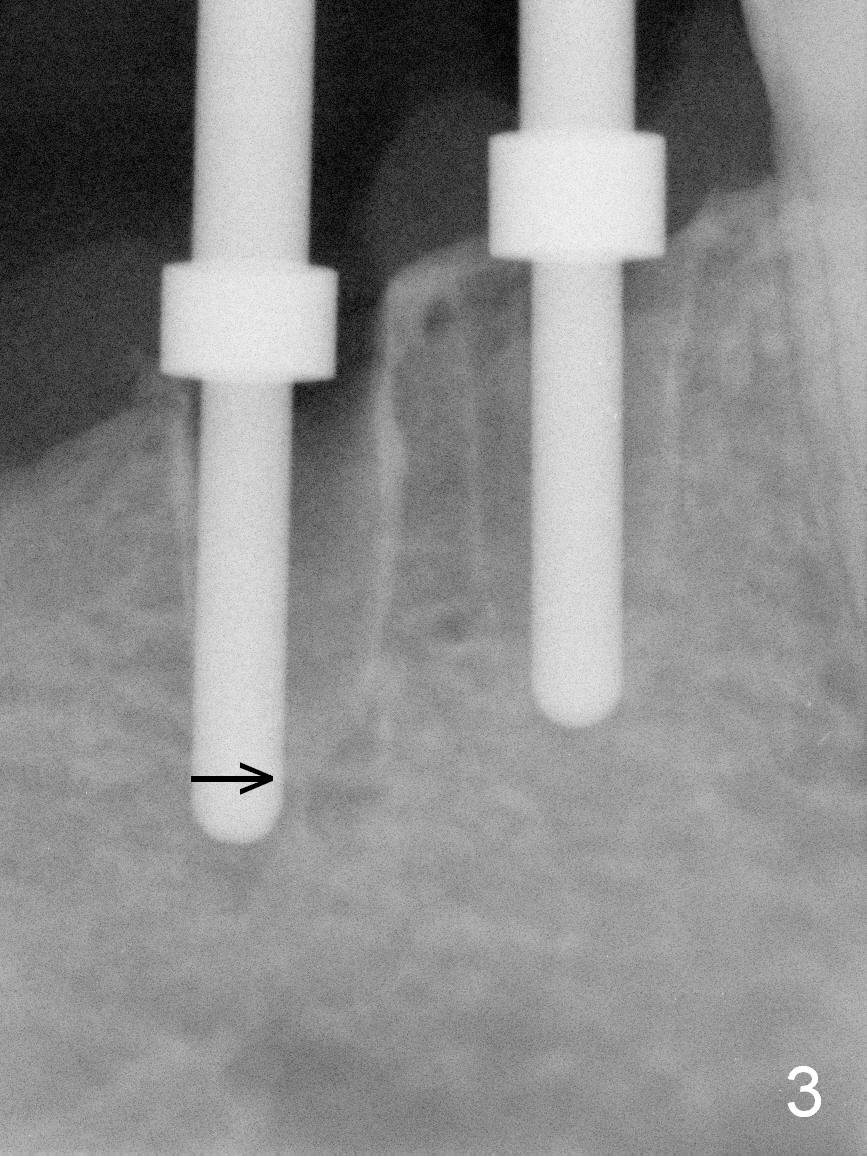

After restoring the implant at the site of #20, the patient returns for #28,29 implant placement (Fig.1,2). Bone level and distance from the Mental Loop (Fig.2 red dashed line) are different. It appears that longer implant can be placed at #28 than that at #29. Parallel pins are placed after initial osteotomy (Fig.3), it appears that the osteotomy at #29 should be moved mesially (arrow). Next PA shows that the position of the osteotomy at #29 is corrected (Fig.4). The position of the implants (4.5x17, 4.5x14 mm) appears ideal (Fig.5). After preparation for an immediate provisional, bone graft is placed in the remaining socket space (Fig.6 *). The splinted provisional is temporarily placed (Fig.7 P). The implant at #29 seems to be buccally placed. After CBCT confirmation, it should be removed for replacement. In addition to moving the osteotomy lingually, there is apparent space (~3 mm) to extend the osteotomy apcially for primary stability (Fig.8 arrow). The apical diameter of the implant is 3 mm.